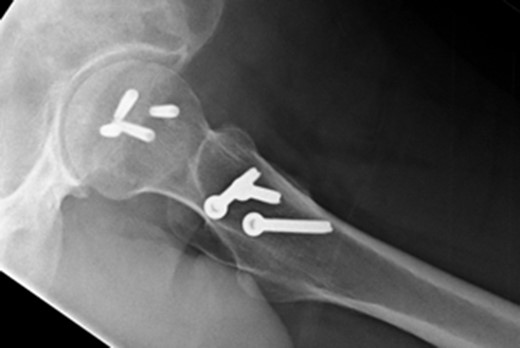

A fit and well man in his 40s had fallen while hiking up a steep hill. He complained of immediate onset, severe left hip pain and inability to move. He was airlifted to our hospital and was found to have shortened externally rotated left leg. Plain X-rays were performed in the emergency department (Fig. 1) identifying isolated fracture–dislocation of the left hip. Computed tomography (CT) was performed while en route to theatre (Figs 2 and 3).

AP radiograph of left hip showing fracture–dislocation of femoral head.